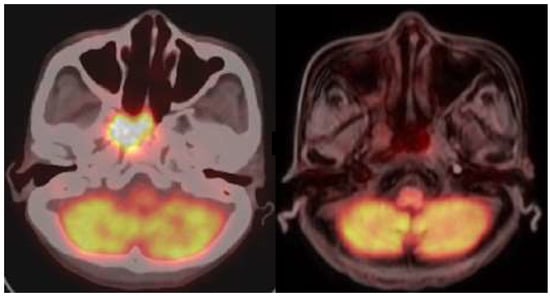

The participants in this study comprised five patients with recurrent HNC. Their demographic information is presented in Table 1 and Table 2. The adverse effects induced by the treatment are presented in Table 3. Patients underwent BNCT followed by fractionated IG-IMRT treatment one month after BNCT. PET/CT scans were utilized to confirm tumor size and treatment response before BNCT, IG-IMRT, and after the completion of the IG-IMRT procedure. The levels of circulating MDSCs were measured by flow cytometry, synchronized with the timing of PET/CT scans. The tumor volume was calculated through 3D image reconstruction from CT images. Before the BNCT treatment, the average percentage levels of PMN-MDSCs, M-MDSCs, and e-MDSCs among MDSCs were 91.23 ± 2.67%, 3.15 ± 2.60%, and 2.70 ± 1.15%, respectively (Figure 1A). To examine the relationship between tumor size and MDSC levels, a correlation analysis was conducted using Spearman’s rank correlation coefficient, and simple linear regression was applied for curve fitting. A significantly positive correlation with tumor volume in patients with recurrent HNC before BNTC treatment was found with the level of circulating M-MDSCs (Figure 1B) but not with the levels of PMN-MDSCs and e-MDSCs (Figure 1C,D). One representative case (patient 1) was demonstrated. A 41-year-old female with recurrent nasopharyngeal cancer underwent single-fraction BNCT with a 16.4 Gy(w) dose on 13 December 2019, followed by 50 Gy fractionated IG-IMRT (25 fractions) from 13 January 2020 to 19 February 2020. Liquid biopsy and PET scans were conducted before BNCT, pre-IG-IMRT, and three months post-IG-IMRT. Pre-IG-IMRT imaging showed a slight tumor size reduction, while post-IG-IMRT imaging confirmed a complete response (CR). Patient 5 also demonstrated the same remarkable therapeutic effect (Figure 2). However, a one-year follow-up of patient 1 showed a sudden increase in M-MDSC levels, and subsequent CT scans revealed tumor recurrence. This patient received subsequent targeted therapy and remains alive as of the writing of this manuscript.

Figure 2.

Imaging results for patient 5. (Left) The positron emission tomography (PET)/computed tomography (CT) image of patient 5 was taken before BNCT treatment. (Right) The PET/magnetic resonance imaging (MRI) scan displayed tumor recurrence in patient 5 following the complete treatment for three months.